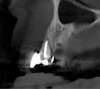

Tomographic images revealed a large tridimensional defect, with vertical and horizontal loss of bone extending to the apical third of teeth Nos. 6 and 8. Additionally, a buccal bone dehiscence was evident on tooth No. 5, and thin labial plates secondary to the orthodontic movement were present in several areas (Figure 3 and Figure 4).

Fig 3. Tomographic images revealed a tridimensional defect extending to the apical third of teeth Nos. 6 and 8, a buccal bone dehiscence on tooth No. 5, and associated thin labial plates.

Figure 3

Fig 4. Tomographic images revealed a tridimensional defect extending to the apical third of teeth Nos. 6 and 8, a buccal bone dehiscence on tooth No. 5, and associated thin labial plates.

Figure 4

Fig 10. Tomographic images of teeth Nos. 6 (Fig 10), 7 (Fig 11), and 8 (Fig 12) clearly showed vertical gains in alveolar height, including in the edentulous area corresponding to tooth No. 7. The apex of tooth No. 8 was located within the soft tissue because it was force-erupted beyond its socket.

Figure 10

Fig 11. Tomographic images of teeth Nos. 6 (Fig 10), 7 (Fig 11), and 8 (Fig 12) clearly showed vertical gains in alveolar height, including in the edentulous area corresponding to tooth No. 7. The apex of tooth No. 8 was located within the soft tissue because it was force-erupted beyond its socket.

Figure 11

Fig 12. Tomographic images of teeth Nos. 6 (Fig 10), 7 (Fig 11), and 8 (Fig 12) clearly showed vertical gains in alveolar height, including in the edentulous area corresponding to tooth No. 7. The apex of tooth No. 8 was located within the soft tissue because it was force-erupted beyond its socket.

Figure 12